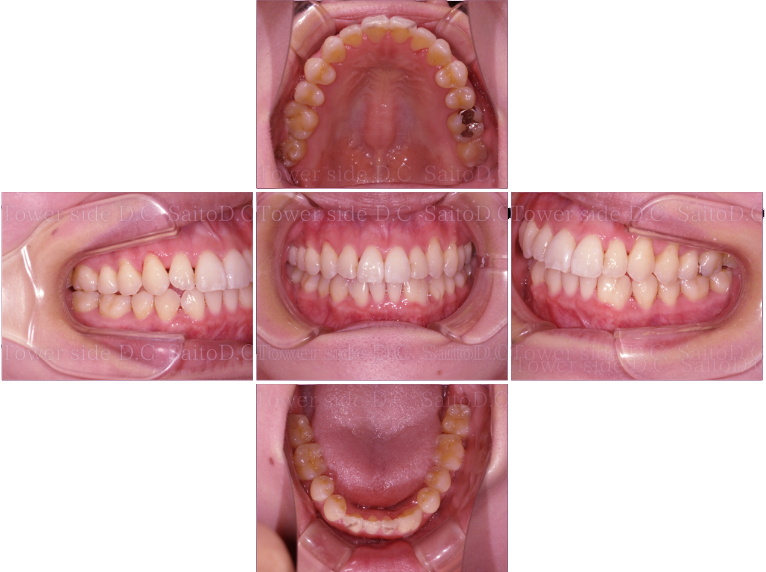

症例(施術前)

症例(施術後)

主訴 上顎側切歯の出っ張りを治したい

状況

• 上顎前歯叢生

• 上顎切歯口蓋側傾斜

• 下顎叢生

治療費 519,200円(税込)(自由診療)

治療期間 8ヶ月

治療内容 歯のディスキングを行い歯列を整えた。叢生は改善され、その後保定装置(リテーナー)を使用し安定している。